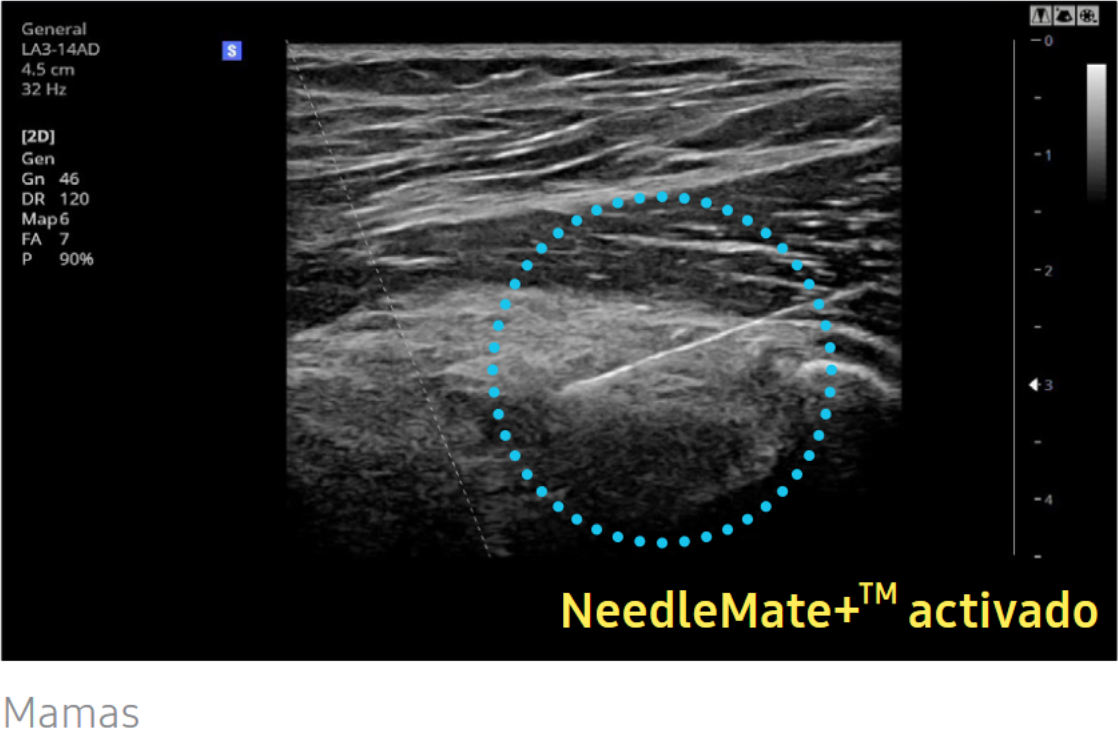

NeedleMate+™

NeedleMate+™ garantiza la orientación precisa de la aguja cuando se realizan procedimientos de intervención comunes. Exploración oblicua. Exploración oblicua permite dirigir la imagen de ultrasonido lineal y mejora la visibilidad de la aguja cuando el ángulo de insonación y la aguja están en un ángulo perpendicular entre sí.